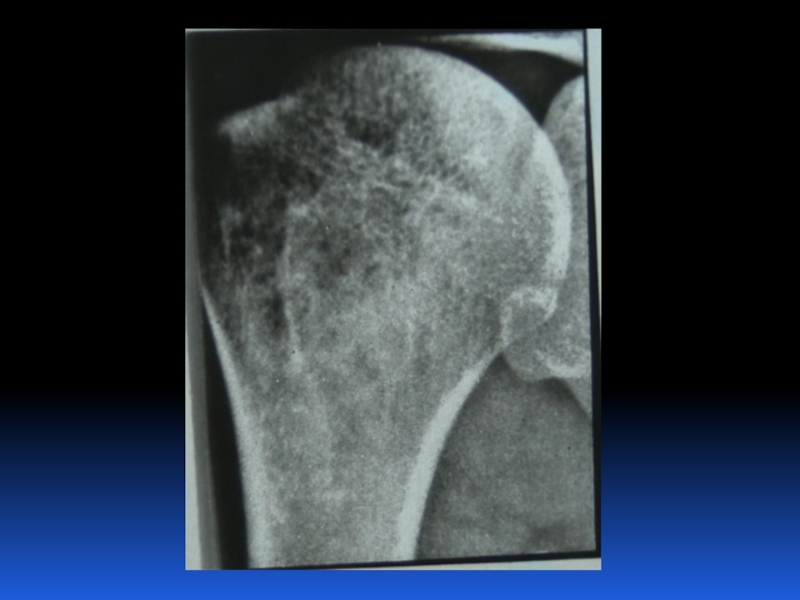

Остеопороз – это системное заболевание скелета, характеризующееся снижением костной массы и нарушением микроархитектоники костной ткани, с последующим увеличением хрупкости костей, со склонностью к патологическим переломам.

Слайд 2 Остеопороз – это системное заболевание скелета, характеризующееся снижением костной

массы и нарушением микроархитектоники костной ткани, с последующим увеличением хрупкости

костей, со склонностью к патологическим переломам.